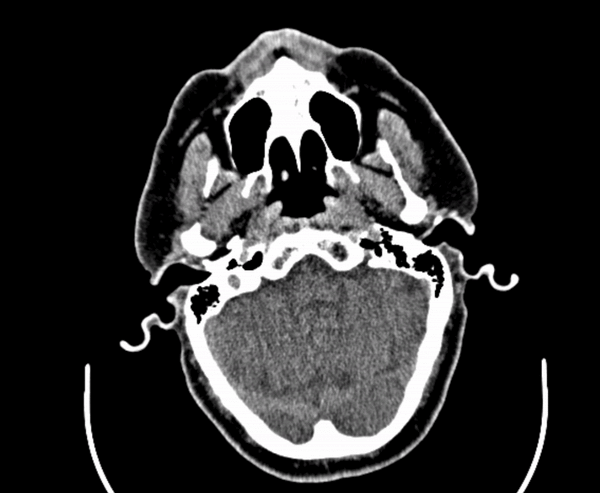

If a picture is worth 1000 words, how many words is a DICOM?

A tool for interactive case presentations